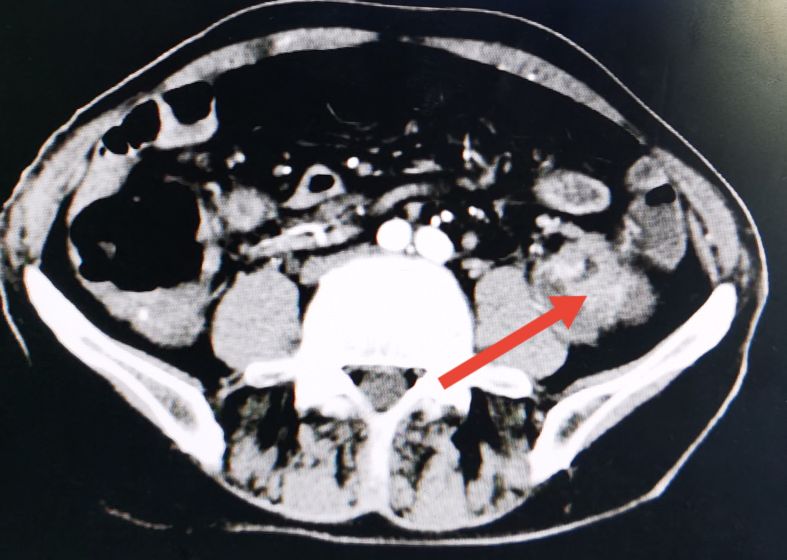

术前CT显示降结肠被肿瘤堵塞后扩张

降结肠肿瘤位置